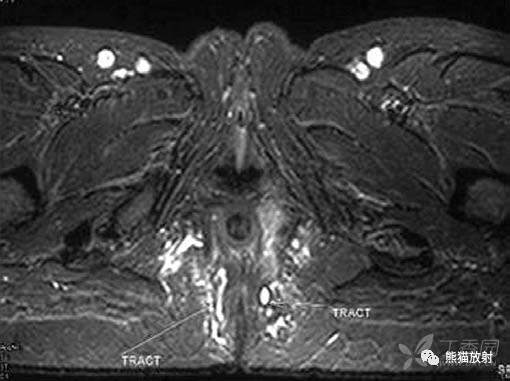

肛门直肠结核

ANORECTAL TUBERCULOSIS

肛周多发小通道,即瘘管形成